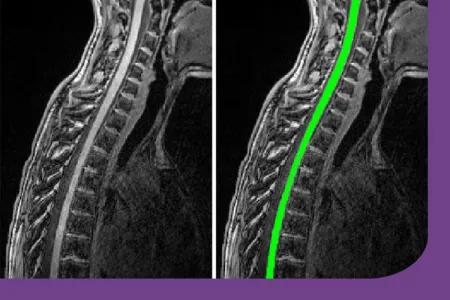

Congratulations to Dr Rozanna Meijboom and colleagues from the MS imaging group, who have recently been awarded funding for a research study to examine changes in the spinal cord of people with multiple sclerosis (MS). Cord-MS Dr Rozanna Meijboom and colleagues have been awarded funding by the MS Society to undertake a pilot (preliminary) study called CORD-MS. In this research, the team will test new and standard MRI scans along the full length of the spinal cord, in people who have recently been diagnosed with MS. The study team will start recruiting participants later this year, looking for people who were diagnosed with relapsing-remitting MS in the last six months.CORD-MS will yield important initial information on spinal cord changes and will help prepare for a larger study on how MS affects the spinal cord early on in the condition.Further information can be found on the Anne Rowling Clinic website:New funding for spinal cord imaging research study Related linksMS SocietyDr Rozanna MeijboomCORD-MSAnne Rowling ClinicEdinburgh ImagingSocial media tags and titlesNew funding for spinal cord imaging research study@EdinUniImaging @AnneRowClinic This article was published on 2025-02-16